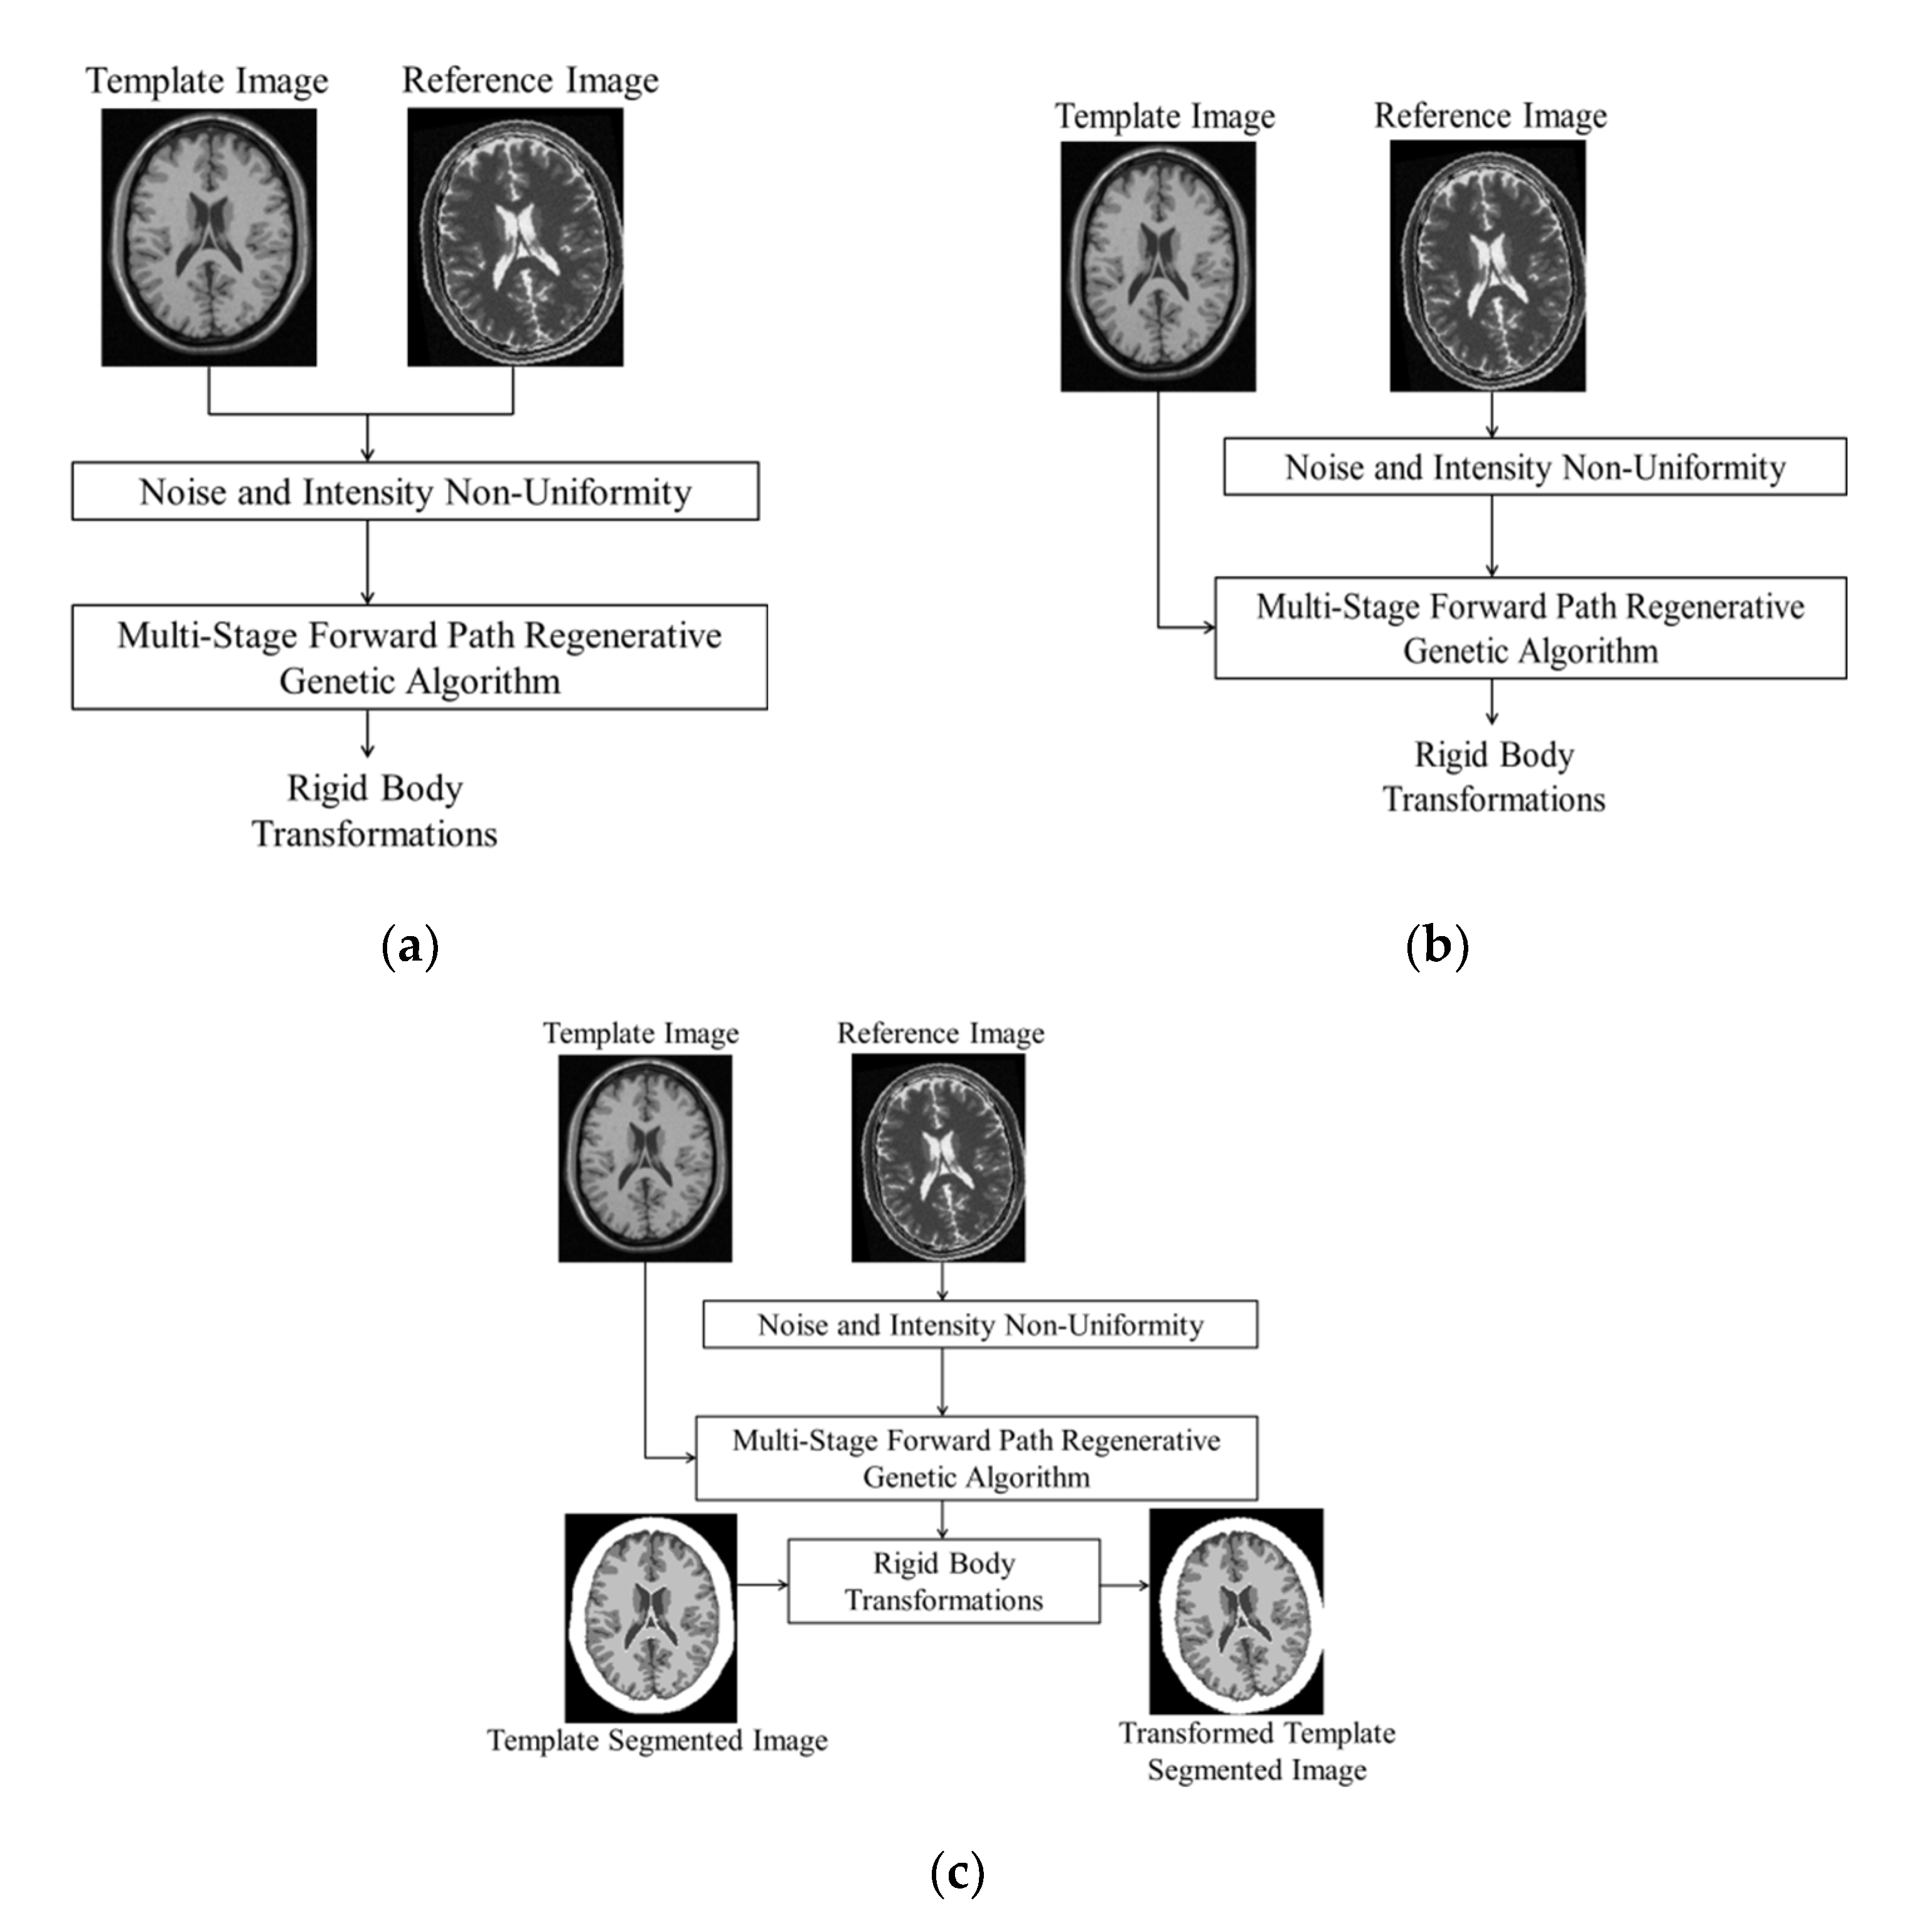

3.4.1. Multi-Stage Forward Path Regenerative Genetic Algorithm